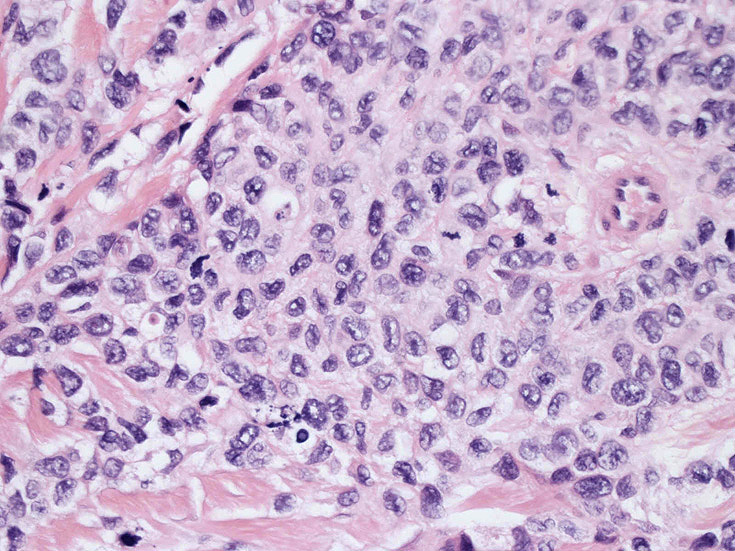

皮膚生検組織。細胞浸潤が表皮, 表皮真皮境界部, 真皮, 皮下組織にびまん性に認められる。血管中心性に結節様の分布があるように見える。

皮膚に異型細胞の浸潤がみられる。異型細胞は表皮内に浸潤するほか、表皮真皮境界部, 真皮, 皮下脂肪組織にもびまん, 結節様の浸潤所見を示す。血管周囲に浸潤、集蔟する所見も多く見られる。 増殖浸潤細胞の核には類円形や腎臓形, またはへこみ, 切れ込み, 溝などを有する多型な核が認められる。クロマチンは粗でvesicularな核が多い。核小体の明らかな核もある。好エオジン性の核内封入体様構造も少数に見られた。mitosisは容易に認められる。hyperchromaticな多型核, bizzarreな細胞が高頻度に認められ異型度は高いと考えられる。細胞質は境界不明瞭, 淡明または泡沫様の 好エオジン性胞体である。